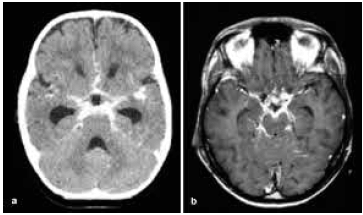

Paciente de 30 anos, previamente saudável, apresenta-se com um quadro clínico de duas semanas de evolução caracterizado por cefaleia persistente, febre baixa e rigidez nucal. O exame do líquido cefalorraquidiano (LCR) revela pleocitose linfocítica, hipoglicorraquia e hiperproteinorraquia.

A tomografia computadorizada (TC) do crânio encontra-se a seguir.

Das seguintes etiologias, a mais provável para os achados clínicos e laboratoriais nesse paciente é: